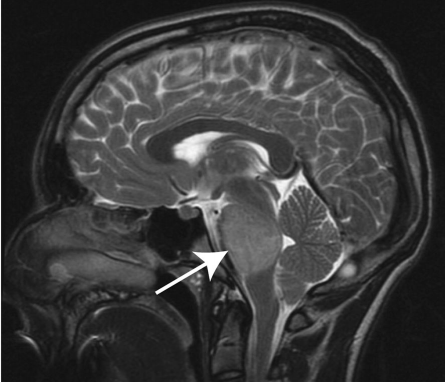

影像学MR解析